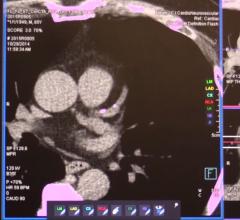

This channel contains news about the Society of Cardiovascular Computed Tomography (SCCT), including coverage of its annual meeting and links to recently released practice guidelines. SCCT is a leading resource for the subspecialty of cardiac computed tomography angiography (CTA or CCTA).